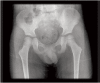

<b>Fig. 1a</b>: Plain AP radiograph of the hips.

Fig. 1a: Plain AP radiograph of the hips.

<b>Fig. 1b</b>: Plain frogview radiograph of the hips.

Fig. 1b: Plain frogview radiograph of the hips.